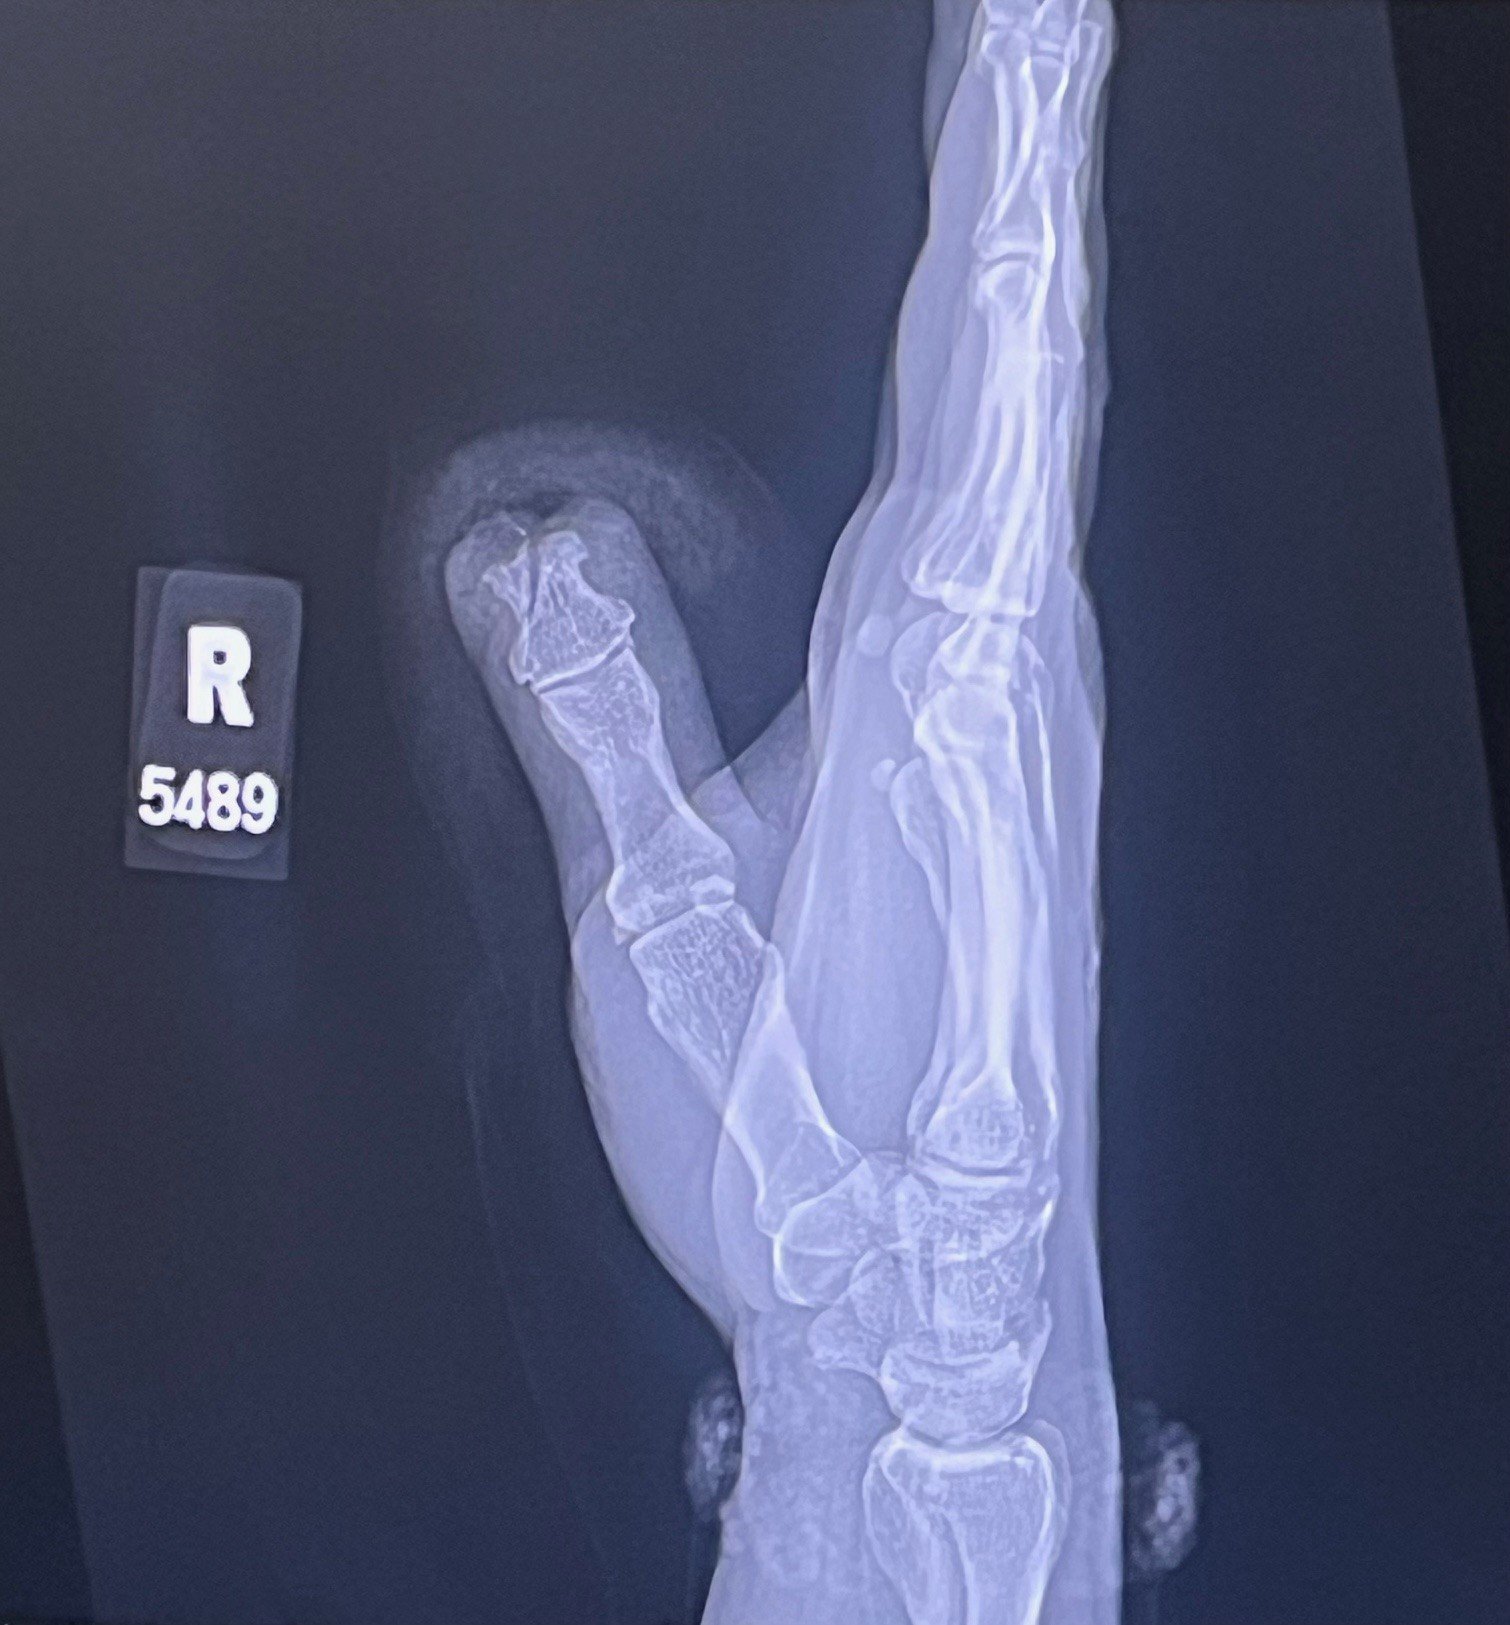

On Friday, March 13, while on a spring break vacation with the family life took a turn. We have two young German Sheperd dogs. Both males and litter mates. For the most part, they are awesome dogs. But sometimes they get into it with one another. Generally, when this happens, I step back and let them have at it until they are both tired. Well, they got into it and my daughter happened to be sitting next to them when they started up. I instinctively grabbed dogs to move them away from her. As I went to grab them, my hand got in the way of two pissed off dogs. My hand modeling days are over, I'm afraid. I suffered what the ER described as a traumatic amputation.

Basically, from where my nail started is now gone. There was no way to save the tip, and the bones below had been shattered. On the 24th, I saw a plastic surgeon in an attempt to save what was left of the finger. I am hopeful that with some time and work, I will be back to my usual level of sucking at guitar...lol! If not, I guess I'll have to slow down, turn the gain down and invest in some tan pants...